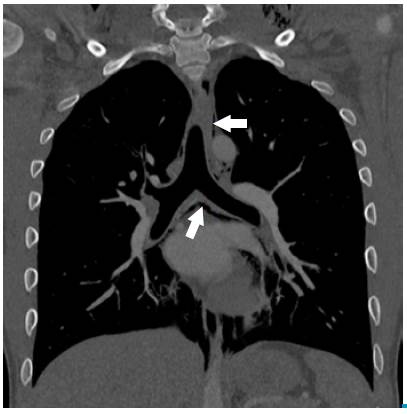

Later, a chest tomography was performed, which showed air in the anterior, middle, posterior and superior mediastinum, reaching the lower neck (Figure 2). Due to the absence of risk factors related to secondary causes, SPM secondary to an acute respiratory infection of viral origin was diagnosed; the patient was maintained under observation, and treatment including oxygen through nasal cannula, respiratory therapy, analgesia and rest was indicated.

Chest tomography, coronal plane: pneumomediastinum, presence of infracarinal and paratracheal air (sepia arrow). Left supraclavicular subcutaneous emphysema is also observed.

Figure 2: Chest tomography, coronal plane: pneumomediastinum, presence of infracarinal and paratracheal air (sepia arrow). Left supraclavicular subcutaneous emphysema is also observed.

Other radiological signs include subcutaneous emphysema, radiolucent lines in the upper mediastinum, pneumoprepericardium, "Naclerio V", extrapleural air sign and, thymic wing sign caused by the delimitation of the thymus in children 16,21. Chest tomography delimits the extension of the pneumomediastinum, and provides information about its etiology and differential diagnoses 21,22.